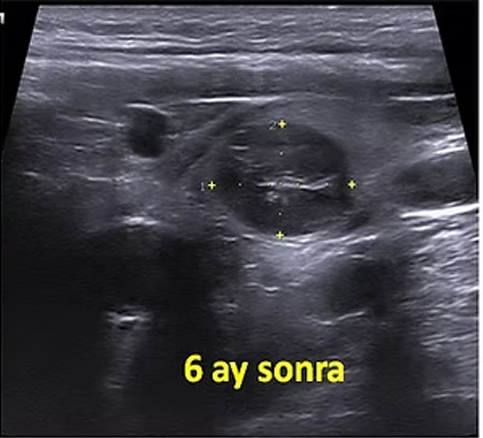

Sol tiroid lobunda rastlantısal olarak saptanan 12 mm çaplı papiller mikrokarsinomu olan 52 yaşındaki kadın hastamızda ultrason eşliğinde perkütan mikrodalga ablasyonu yapıldı. On beş ay sonra, nodül ultrasonda izlenememiştir.